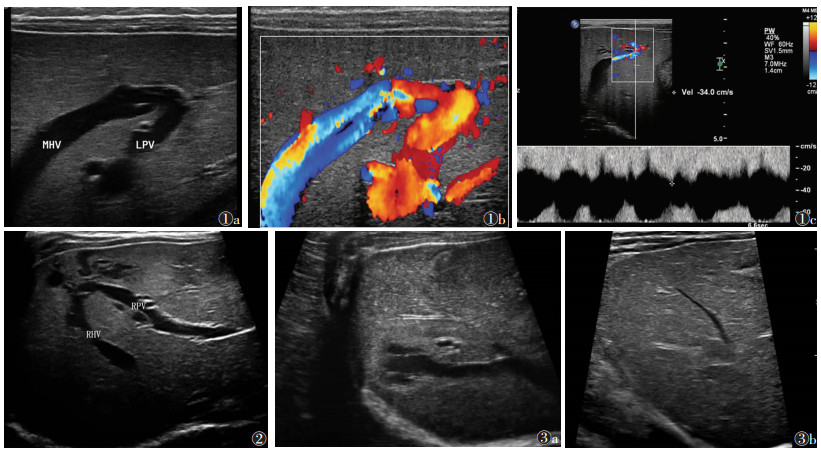

2 结果 2.1 二维超声表现病变均位于肝实质内近肝脏表面或叶段边缘,1例单发,7例多发,二维超声呈管型、囊状及不规则无回声,大小1.1 cm×2.4 cm~2.5 cm×3.4 cm。其中肝右叶1例,为门静脉右前叶支-肝右静脉分流;肝左叶3例,1例为门静脉左支-肝中静脉分流(图 1a),2例为门静脉左内叶支-肝左静脉分流;左、右叶均受累4例,2例为门静脉右前支-肝中静脉分流并门静脉左外叶下段支-肝左静脉分流,1例为门静脉右支-肝右静脉分流并门静脉左内支-肝中静脉分流,1例为门静脉右支-肝右静脉、肝中静脉分流并门静脉左内支-肝左静脉分流(图 2)。8例均伴肝内多发血管瘤。病变处门静脉端分流口内径范围0.07~0.26 cm,肝静脉端分流口内径范围0.12~0.22 cm。

| 图 1 男,23 d 图 1a 二维超声示门静脉左支与肝中静脉直接相通 图 1b 彩色多普勒超声可见自门静脉流向肝静脉的血流信号 图 1c 频谱多普勒超声于肝静脉端录及连续静脉样血流频谱,最高流速34.0 cm/s 图 2 女,42 d,二维超声示门静脉右支与肝右静脉直接相通 图 3 女,22 d 图 3a 初次检查时肝右静脉远端呈囊状扩张 图 3b 6个月后复查,肝右静脉远端囊状扩张逐渐消失(MHV,肝中静脉;LPV,门静脉左支;RHV,肝右静脉;RPV,门静脉右支) |

彩色多普勒超声检查可见自门静脉分支至肝静脉的红蓝交替的血流信号,无搏动性(图 1b),脉冲多普勒超声在分流门静脉探及连续性低速带状血流信号,在引流的肝静脉内可探及连续性单向血流频谱(图 1c),平均流速30.5 cm/s,最高流速65.0 cm/s。2例引流肝静脉内径增宽,分别为1.2、1.5 cm,1例呈囊状扩张。

2.3 随访结果随访1例,男,出生后34 d因头、面、颈、躯干、四肢、阴囊、会阴等全身皮肤多发血管瘤就诊,入院MSCT及超声诊断CIPSVS Ⅳ型。肝右静脉、肝中静脉远端扩张呈囊状(图 3a),门静脉右前支与肝中静脉分流并门静脉左外叶下段支与肝左静脉相通。患儿遵医嘱口服普萘洛尔1.5 mg·kg-1·d-1,分3次8 h口服,3 d后增至2.0 mg·kg-1·d-1,并分别于2、4、6个月后门诊复查,肝右静脉、肝中静脉远端囊状扩张逐渐缩小(图 3b),皮肤及肝内血管瘤逐渐消失,门静脉-肝静脉分流分支逐渐闭合,全身血管瘤消失。